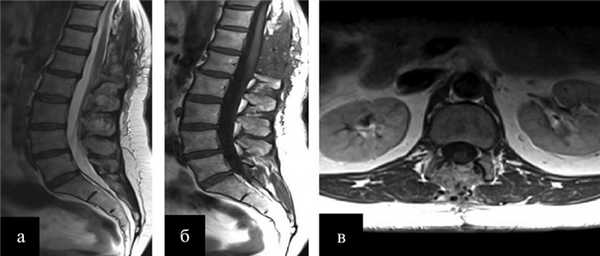

Через 12 мес после операции было выполнено контрольное МРТ-исследование, на котором выявлена та же МР-картина, что и перед операцией (рис. 1).

Рис. 1. Гемангиобластома корешка L4. На серии МРТ, выполненных в сагиттальной, фронтальной и аксиальной проекциях в режиме T2 (а, б, в), определяется экстрадурально расположенное гипоинтенсивное объемное образование на уровне L4—L5 позвонков с гиперинтенсивными очагами и паравертебральным ростом влево по типу «песочных часов» (опухоль указана белыми стрелками). В сагиттальной и фронтальной проекциях (а, б) обращает на себя внимание выраженная сосудистая сеть (указана красными стрелками), которой в Т2-режиме соответствуют множественные зоны гипоинтенсивного сигнала.